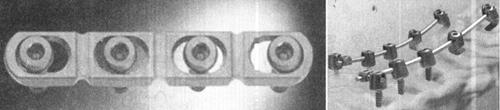

七、颈椎融合器

一直以来,人们都在为克服自身取骨的不足,避免常规植骨方法出现的骨块吸收、塌陷、松动移位突出或突入椎管的严重并发症,不断寻求新的植骨方法。随着80年代后期椎间融合器(Interbody fusion cage)在腰椎应用成功,颈椎椎间融合器的研究文献也相继报道。颈椎融合器的研制目的是获得早期的稳定性,减少术后外固定的使用;减少自体取骨的并发症;促进融合,增加融合率。

(一)颈椎椎间融合器按结构、形状和设计理念分类

(1)钛网:由钛合金制成的网状融合器。优点是通用性强,符合承重分担的原理,植骨接触面积大,有多种形状且可以按需要弯曲或修剪(图13-30A)。缺点是边缘锐利,接触面积小,支撑作用较小,也易于发生终板塌陷。

图13-30 各种颈椎融合器(A.钛网;B.Sofamor的Affinity圆形融合器;C.Sofamor的Cornerstone方型融合器)

(2)圆筒状或螺纹状:该形状融合器类似于Cloward的柱状植骨技术(dowel techniques),为中空表面带螺纹及孔隙的筒状结构。植入前、中空部分充填以松质骨。典型的如BAK-C Cage和Affinity Cage等(图13-30B)。但这类融合器植骨接触面积小影响融合率,易发生终板塌陷,逐渐被新型融合器代替。

(3)环状或方形:此类融合器的设计源于三面皮质骨的椎体间植骨,其中空部分填以松质骨,盒式设计保证了植骨与相邻椎体的接触以利于融合,有防止脱出的倒齿设计,提供良好的应力传递表明,减少应力遮挡。典型的如AcroMed I/FCage、SynCage和Depuy I/FCage、Sofamor的Cornerstone等(图13-30C)。